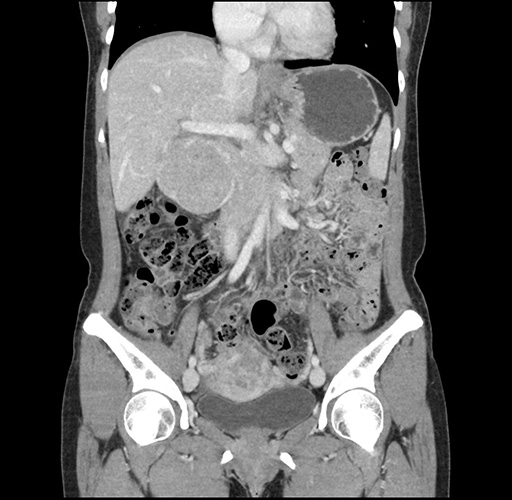

Imaging Analysis

Look through the patient's CT scan to identify any areas of concern for the necessary procedure.

Based on your CT findings, which issue(s) would give reason for "planned slowing down moment(s)" in this case?

Considering a standard left lateral sectionectomy procedure, what step(s) of the operation would you do differently in this case ?